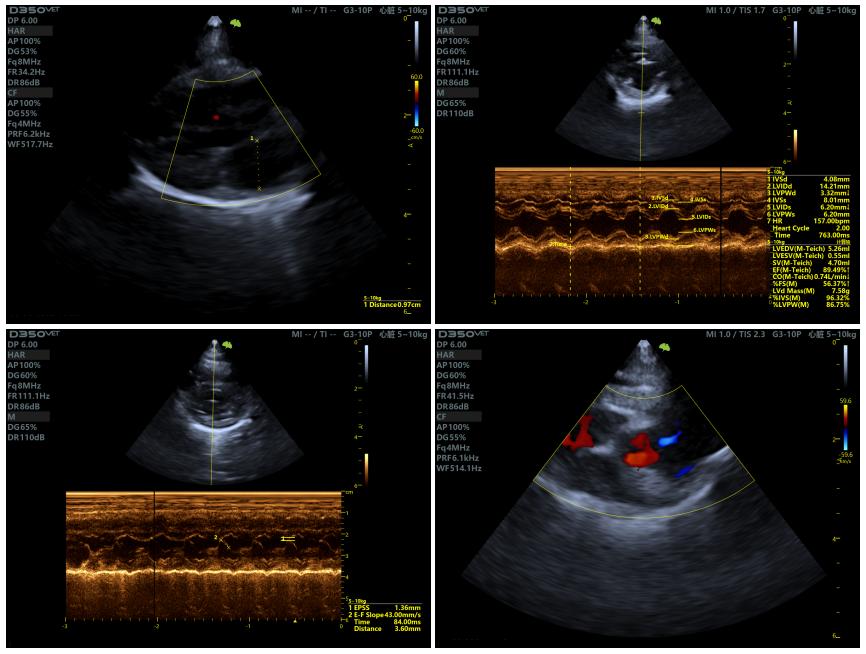

2、生化与心脏检查

印象:无异常,符合手术条件